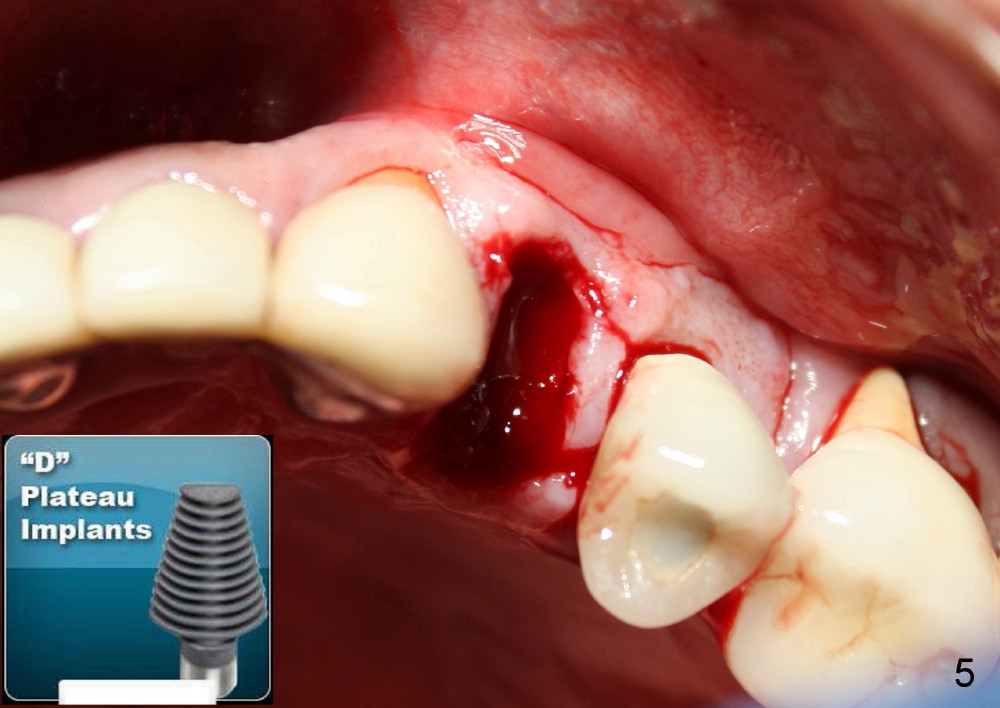

The socket of an upper first premolar is oval (Fig.5), whereas majority of implants are rounded. It is always a mismatch. An implant that matches the shape of the socket most closely is "D" Plateau Implant (Fig.5 insert, Fig.6). The D implant that is appropriate for your case is called D2. It is 20 mm long (Fig.4). On cross section is 5.5 mm wide and 3.5 mm tall at crest (widest portion, Fig.6 insert). The D implant is tapped in. Immediate provisional can be installed. Are you interested in the D implant? Crown forms are needed for the provisional.